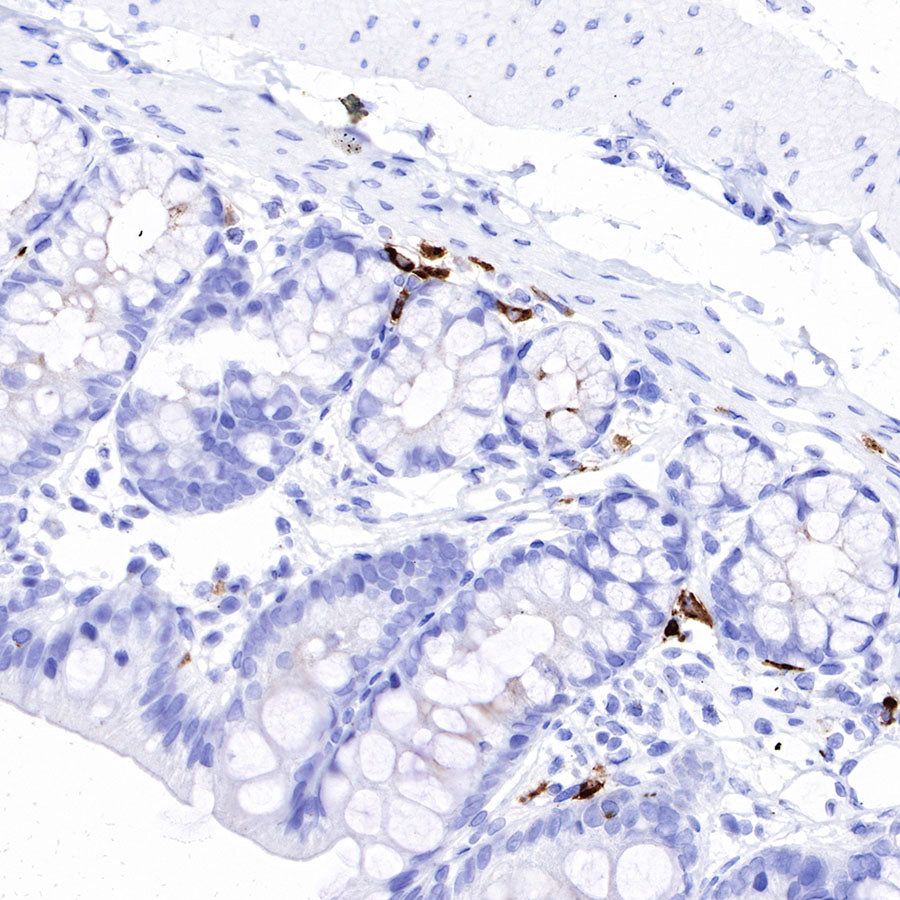

Immunohistochemistry

IHC shows positive staining in paraffin-embedded human tonsil. Anti-IGJ antibody was used at 1/1600 dilution, followed by a HRP Polymer for Mouse & Rabbit IgG (ready to use). Counterstained with hematoxylin. Heat mediated antigen retrieval with Tris/EDTA buffer pH9.0 was performed before commencing with IHC staining protocol.

IHC shows positive staining in paraffin-embedded human spleen. Anti-IGJ antibody was used at 1/1600 dilution, followed by a HRP Polymer for Mouse & Rabbit IgG (ready to use). Counterstained with hematoxylin. Heat mediated antigen retrieval with Tris/EDTA buffer pH9.0 was performed before commencing with IHC staining protocol.